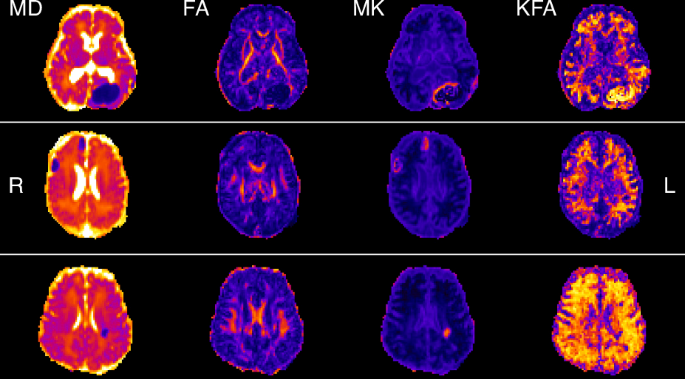

DKI data were quality controlled by removing image volumes and associated gradient directions containing excessive head motion or signal drop-out artifacts. Cleaned DKI data were processed using PyDesigner42 resulting in rotationally invariant parametric maps derived from the estimated diffusion and kurtosis tensors. Diffusion parameters calculated and used in our analysis included MD, FA, MK and KFA. Representative parametric maps in a single neonate are shown to highlight the differences in diffusivity and kurtosis metrics in Fig. 2. Example images of neonatal brain infarcts as viewed with both diffusivity and kurtosis are provided in Fig. 3.

Kurtosis provides complimentary information that supplements and does not duplicate diffusivity. On the top row, a 41-week GA neonate experienced a left occipital lobe hemorrhage that developed during ECMO. In the middle row, MRI in a 37-week GA neonate shows signal abnormalities in the ventrolateral thalami and posterior putamen, along with right frontal, parietal, temporal and cerebellar hemorrhages. The infant also had a right sided grade 2 IVH. Lastly, the neonate on the bottom row is 40 week GA with a left posterior parietal lobe hemorrhagic venous infarct. All three neonate images shown come from the NVD-A cohort where the infarcts were imaged within the first week of life. These images demonstrate a stark contrast between the diffusivity and kurtosis metrics. While the infarcts are represented as a void on the MD and FA, they are bright on the MK and KFA, illustrating the increased complexity within the infarct. This points to a potential use for MK and KFA as more sensitive markers of recovery dynamics within damaged brain tissue.